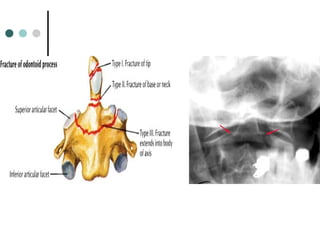

ODONTOID FRACTURE

 Fracture of the odontoid (dens) process of C2

 Best seen on the lateral view

 Types :

 Type I – Fracture through superior portion of dens (Stable)

 Type II – Fracture through the base of the dens (most common,

most dangerous, prone to non-union; Unstable; requires ORIF

 Type III – Fracture that extends into the body of C2 (Stable)

best prognosis